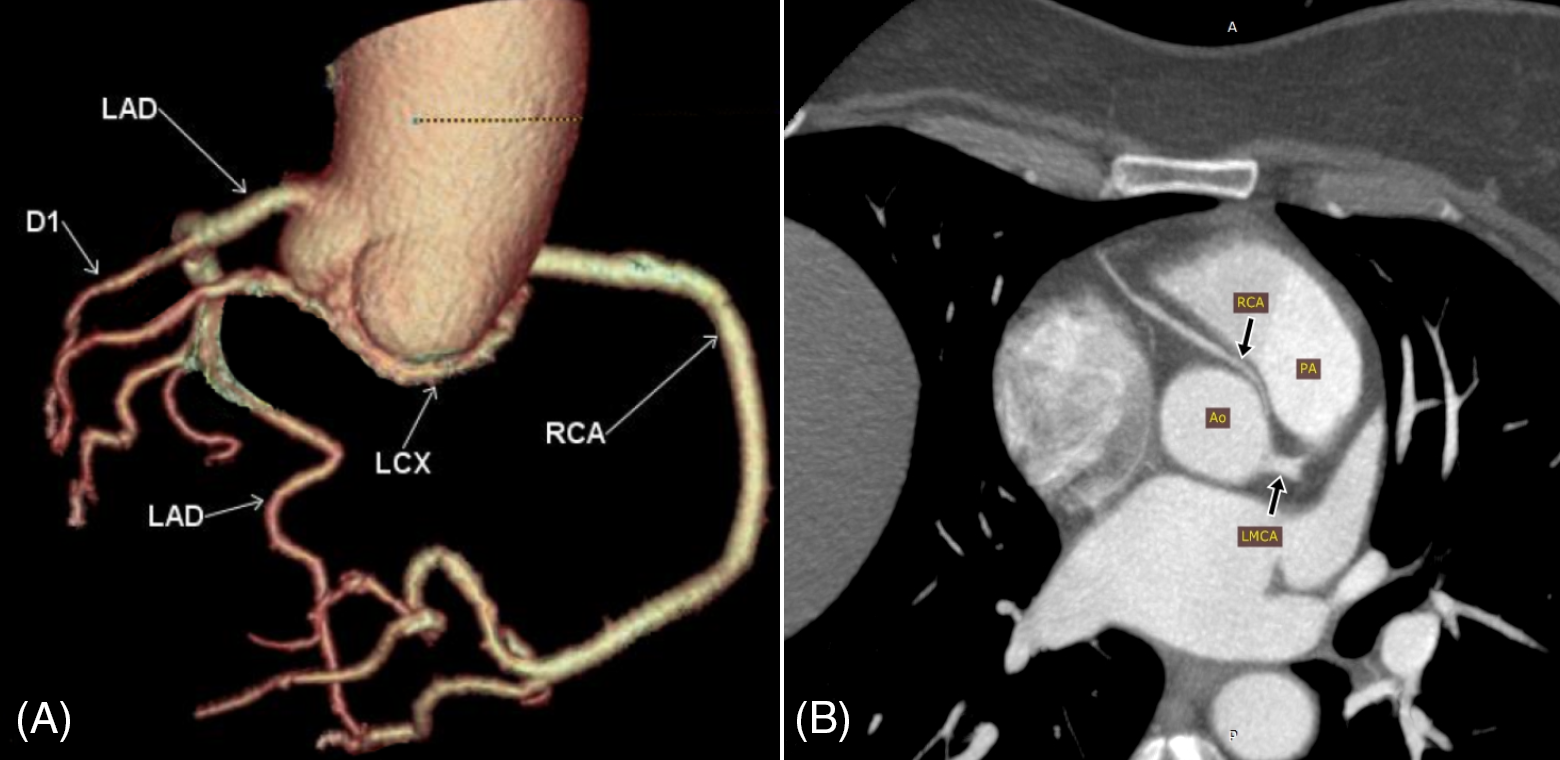

Group 2 included a myocardial bridge (MB), defined as a major epicardial artery running into the myocardium (Fig. 3).

Figure 3: Three-dimensional surface rendering of coronary CT angiography showing myocardial bridges. (A) Distal left anterior descending artery myocardial bridge (LAD MB). (B) The RCA passes within the wall of the right atrium (RCA MB) rather than the usual course in the right atrioventricular groove

Group 3 included the anomalous course of the coronary arteries (Fig. 4).

Figure 4: Abnormal course (and origin) of coronary arteries. (A) Volume rendering (VR) of the coronary artery tree showing the left circumflex artery (LCX) arising from the right coronary cusp and coursing inferior to the posterior aortic cusp towards the left side (RCA; right coronary artery, LAD; left anterior descending artery arising directly from the left cusp, D1; first diagonal branch). (B) Maximum intensity projection (MIP) showing the right coronary artery (RCA) arising anterior to the left coronary cusp and passing between the aorta (Ao) and the pulmonary artery (PA) in the interarterial groove (LMCA; left main coronary artery)